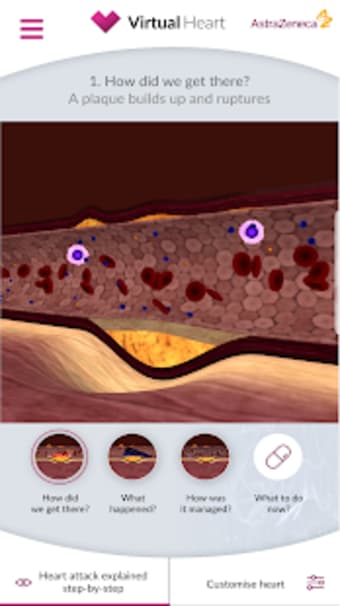

En gratis app för Android, av AstraZeneca Pharmaceuticals.

Virtual Heart - ANZ är en gratis programvara för Android, som ingår i kategorin 'Medical'.Om Virtual Heart - ANZ för Android